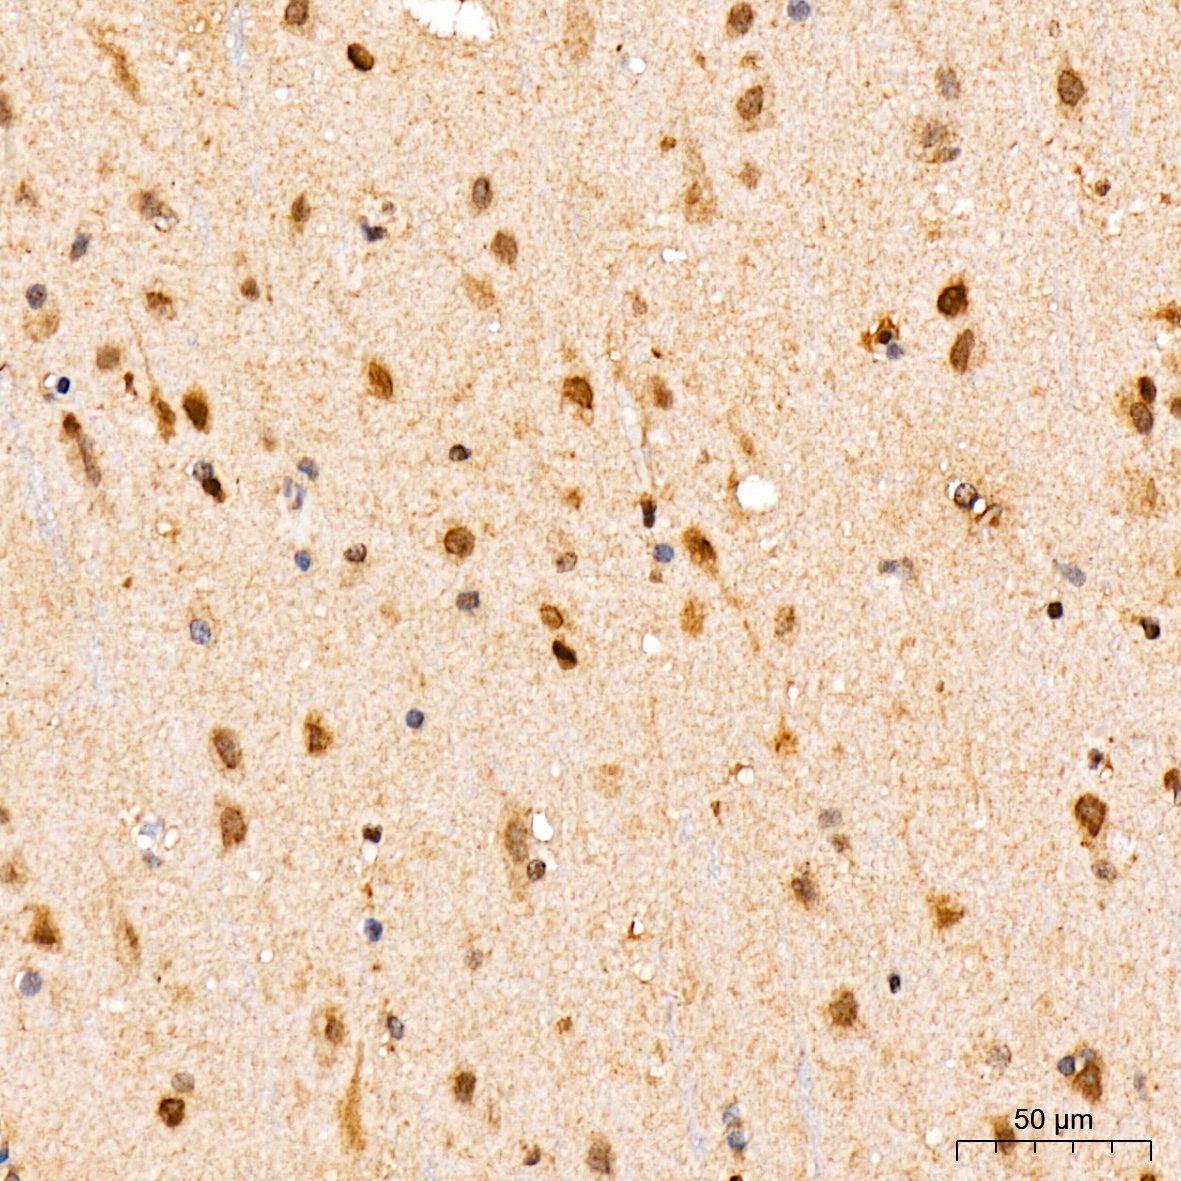

| Immunohistochemistry analysis of paraffin-embedded Human brain tissue using [KO Validated] STAT3 Rabbit mAb (A19566) at a dilution of 1:200 (40x lens). High pressure antigen retrieval was performed with 0.01 M citrate buffer (pH 6.0) prior to IHC staining. |